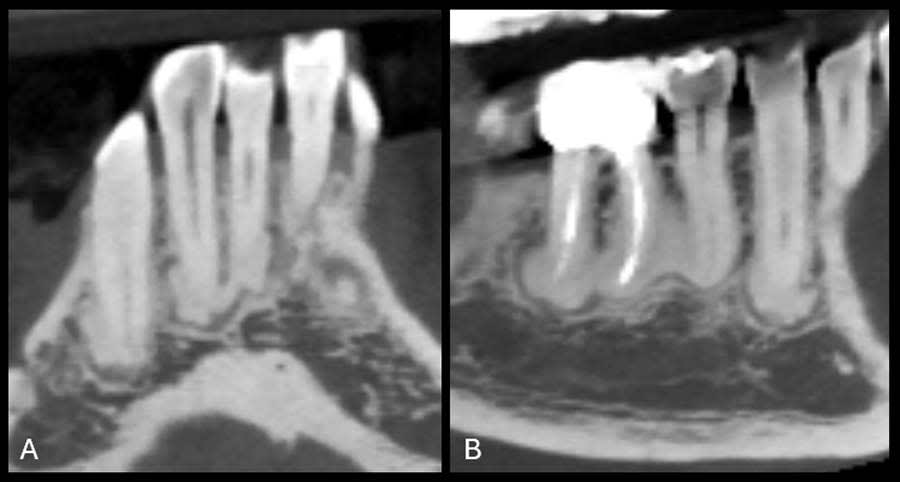

To establish a differential diagnosis, in addition to testing both teeth Nos. 29 and 30 for endodontic/periodontal disease, the clinician reviewed the patient’s systemic health and referenced a previous FMX captured in 2018, which demonstrated a progression of cementum deposition (Figure 2, left). Cementum deposition progression to concrescence of Nos. 25/26 could also be noted (Figure 3).

A review of the patient’s dental history revealed that she was never diagnosed with periodontitis, and bone loss had been attributed to physiological aging, gingival recession, and increased biomechanical loading. Tooth No. 19 had been extracted due to secondary caries and not periodontal conditions. The 2018 FMX exhibited generalized hypercementosis, including the mandibular right, mandibular central, and maxillary left posterior areas, and no evidence of concrescence (Figure 4). In 2022, the patient had a cone-beam computed tomography (CBCT) scan in preparation of the No. 19 implant where hypercementosis with concrescence could be seen with Nos. 25/26 and 29/30 (Figure 5).